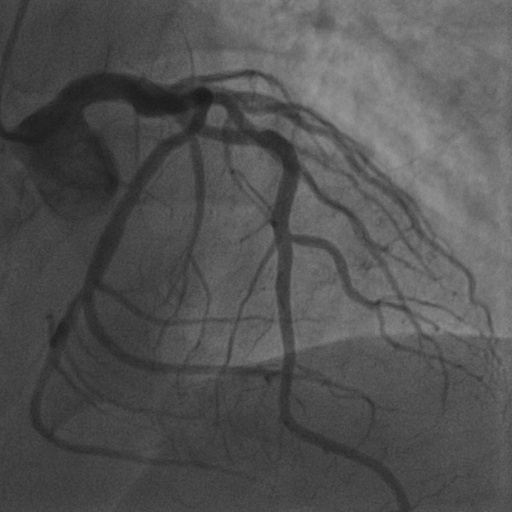

4.1 XACV Dataset

We collect 111 complete records of coronary artery X-ray videos, encompassing the injection, flow through the blood vessels around the heart, and dissipation of the contrast agent. Subsequently, we establish the XACV (X-ray Angiography Coronary Video) dataset. Each video consists of varying numbers of high-resolution coronary artery X-ray images. We invite experienced radiologists to annotate the vascular regions, focusing on one or two frames where the contrast agent is most prominent in each video. The XCAD dataset contains only a single image, and the CADICA video dataset does not provide corresponding ground truth. Therefore, in the following experiments, we conduct all the analyses on our collected XACV dataset and the corresponding GT for each sequence. In Figure 5, we show that compared to other publicly available datasets, XCAD [33] and CADICA [19], our dataset exhibits finer annotations in the vascular regions, providing an advantage for future related tasks. The development and use of our dataset have been approved by our institution’s IRB.